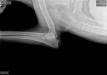

OFA hips and elbows 11.13.18